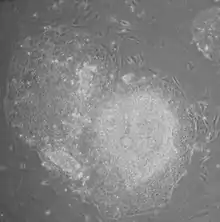

- Morphology: iPSCs were morphologically similar to ESCs. Each cell had round shape, large nucleolus and scant cytoplasm. Colonies of iPSCs were also similar to that of ESCs. Human iPSCs formed sharp-edged, flat, tightly packed colonies similar to hESCs and mouse iPSCs formed the colonies similar to mESCs, less flat and more aggregated colonies than that of hESCs.